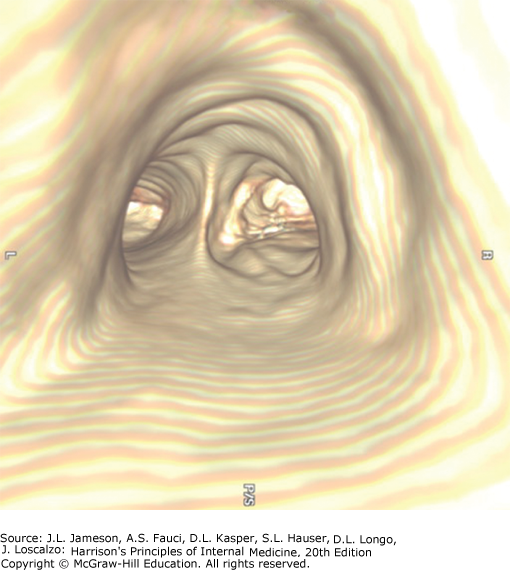

| 11 | Be familiar with diagnostic procedures in respiratory disease | Diagnostic modalities include imaging (chest X-ray, CT/helical CT, MRI, ultrasound, nuclear medicine/V-Q scan, PET scan, virtual bronchoscopy) and tissue-sampling techniques. CT is superior to plain film for mediastinal disease, emphysema characterization, and lung cancer staging. MRI excels at vascular assessment without contrast. |

| Virtual Bronchoscopy | 3D reconstruction from MDCT data. Visualizes airways down to 6th–7th generation. Digital storage allows reanalysis. Assesses airway relationship to mediastinal structures | Airway stenosis assessment (extent and length), pre-procedure planning for therapeutic bronchoscopy |

Flexible Fiberoptic Bronchoscopy

Outpatient procedure performed under conscious sedation. Scope passed through mouth or nose, between vocal cords, into trachea. Flexible tip allows visualization to subsegmental bronchi.

Identifies: endobronchial tumors, granulomas, bronchitis, foreign bodies, bleeding sites.

Sampling methods:

- Washing: Sterile saline instilled onto lesion surface, suctioned back for cytology and cultures

- Brushing: Small brush at end of cable recovers cellular material for cytologic analysis

- Biopsy: Forceps at end of cable obtains tissue for histopathologic analysis